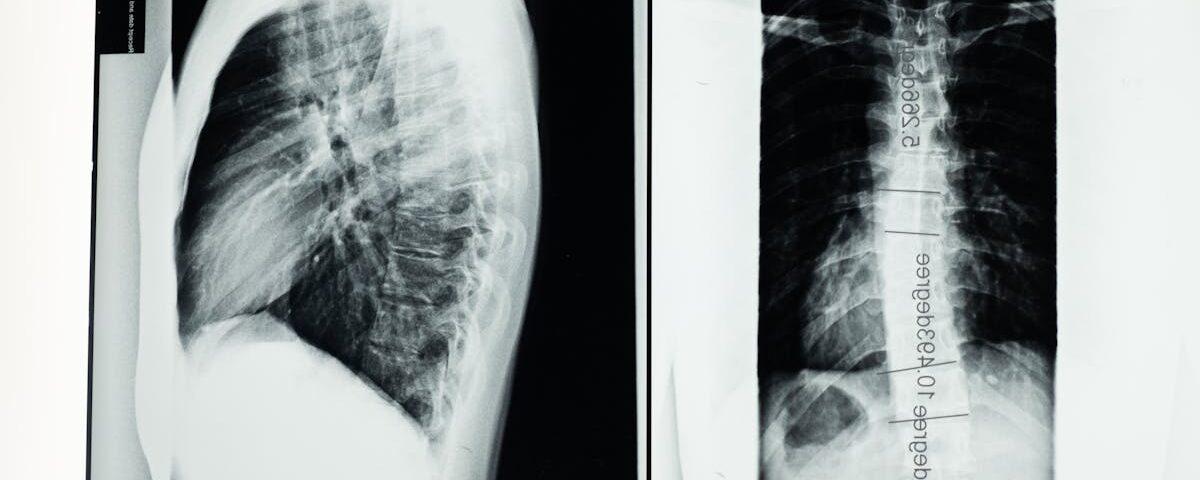

La décompression spinale peut être bénéfique pour de nombreuses conditions liées à la colonne vertébrale. Elle est couramment utilisée pour traiter la sténose spinale, les douleurs chroniques, ainsi que les hernies discales. Chaque cas est unique, et un diagnostic détaillé est essentiel pour déterminer l’approche thérapeutique adéquate.

La décompression spinale repose sur le principe d’appliquer des forces de traction spécifiques sur la colonne vertébrale. En créant un espace entre les vertèbres, cette technique permet de diminuer la pression sur les nerfs et les disques endommagés. Cela intervient particulièrement dans le cas de pathologies comme l’herniediscale ou la sténose spinale, où la pression sur les nerfs peut générer de vives douleurs. En favorisant un meilleur équilibre vertébral, non seulement le patient ressent une diminution de la douleur, mais il bénéficie également d’une meilleure mobilité.

La décompression spinale est particulièrement bénéfique pour les individus souffrant de problèmes vertébraux comme les hernies discales, la sténose spinale, ou les douleurs lombaires chroniques. Cependant, les personnes souffrant d’autres douleurs neuropathiques peuvent également trouver un relâchement grâce à cette technique. Une évaluation préalable par un professionnel de santé est essentielle pour déterminer si cette méthode est adaptée à chaque patient.